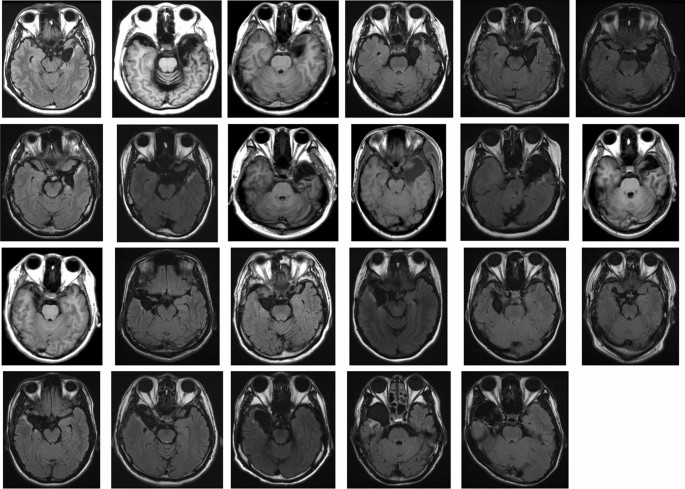

To investigate this hypothesis, we tested a group of patients with unilaterally resected medial temporal lobe structures, including the amygdala (Fig.Ā 1), using a visual-search paradigm. Normal facial expressions of anger and happiness in Caucasian models selected from a standard facial-expression database23, and their corresponding anti-expressions, were the target stimuli among a crowd with neutral expressions presented to the unilateral visual field (Fig.Ā 2). Because the anti-expressions showed neutral emotions, but had visual feature changes equivalent to those between normal emotional and neutral expressions14, they allowed us to compare emotional and neutral facial expressions while controlling for the effects of basic visual processing. Because visual images presented in a unilateral visual field are primarily processed in the contralateral hemisphere24, we compared the RT required to detect normal expressions and anti-expressions between intact- and resected-hemisphere stimulation conditions. This visual half-field paradigm has been shown to effectively reveal the emotional and social processing profiles in one hemisphere of healthy participants25,26,27,28,29,30,31, split-brain patients32,33,34,35,36, and patients with unilateral medial temporal structure resection37,38. To confirm the emotional impact of normal expressions and anti-expressions, we also obtained subjective ratings of the stimuli from the patients, in terms of valence and arousal, and also investigated familiarity and naturalness as possible cognitive confounding factors39. Additionally, the performance of age-, sex-, and handedness-matched healthy controls was tested. We independently analyzed the data from the controls and compared their RTs for the detection of normal expressions versus anti-expressions between the left- and right-hemisphere stimulation conditions.

The patient group included 23 patients (8 females, 15 males; meanā±āSD ageā=ā32.7ā±ā12.8Ā years) with medial temporal lobe structures that were unilaterally resected due to pharmacologically intractable seizures. Although three additional candidates were tested, their data were not analyzed because they displayed a visual deficit (nā=ā1; see āProcedureā), withdrew from the study (nā=ā1), or slept during the task (nā=ā1). We determined the sample size using an a priori power analysis. We used G*Power software58 (ver. 3.1.9.2) and assumed to contrast the intact- versus resected-hemisphere stimulation with an α level of 0.05, power of 0.80, and effect size d of 0.5 (strong). The results indicated that 21 participants would be required. All patients had undergone the surgical procedure more than 1Ā year before the experiment. Seizures were well controlled in most of the patients (nā=ā17, 3, 2, and 1 for Engel Classes59 I, II, III, and IV, respectively), and all were mentally stable during the experiments. Handedness was assessed using the Edinburgh Handedness Inventory60 (meanā±āSD laterality quotient [LQ]ā=ā76.2ā±ā38.2); most patients were right-handed (i.e., LQā>ā0; nā=ā22). Of the 23 participants, 12 (5 females, 7 males; meanā±āSD ageā=ā31.6ā±ā12.1Ā years; meanā±āSD LQā=ā89.3ā±ā12.3) and 11 (3 females, 8 males; meanā±āSD ageā=ā33.9ā±ā14.0Ā years; meanā±āSD LQā=ā60.7ā±ā50.8) had undergone resection in the left and right hemispheres, respectively. The resection method was selective amygdalohippocampectomy, which included the amygdala, anterior part of the hippocampus, and anterior parahippocampal gyrus, in 17 patients, and anterior temporal lobectomy, which included the amygdala, anterior part of the hippocampus, anterior temporal lobe neocortex (4ā5Ā cm from the temporal pole), and anterior parahippocampal cortex, in six patients. Postsurgical magnetic resonance imaging confirmed resection of the target regions in all patients (Fig.Ā 1). The healthy control group included 23 adults (8 females, 15 males; meanā±āSD ageā=ā28.0ā±ā5.4Ā years; meanā±āSD LQā=ā84.1ā±ā16.3). The control group was matched with the patient group for age (t(44)ā=ā1.67, pā=ā0.115), sex (Ļ2(1)ā=ā0.00, pā=ā1.000), and LQ (t(44)ā=ā0.91, pā=ā0.369). All participants had normal or corrected-to-normal visual acuity, and all provided written informed consent following a full explanation of the procedure. This study was approved by the Ethics Committee of Shizuoka Institute of Epilepsy and Neurological Disorders, and was conducted according to institutional ethical provisions and the Declaration of Helsinki.